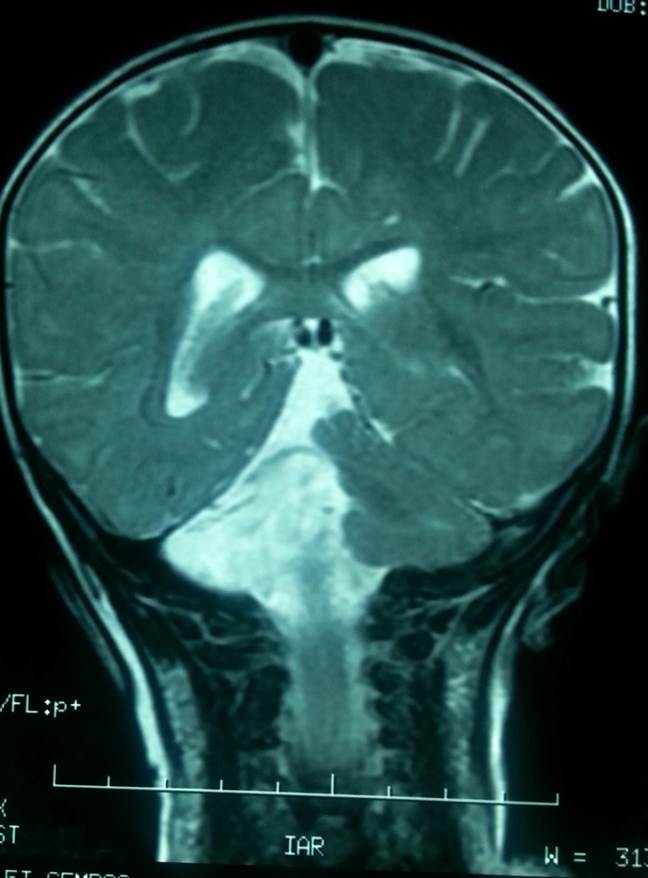

Presentamos el caso de una niña de 9 años, tercera hija de padres sanos no consanguíneos. Durante el segundo mes de embarazo su madre padeció una trombosis venosa profunda que requirió tratamiento con heparina y medias de compresión. Nacida a término con peso adecuado, no necesitó reanimación neonatal. Se alimentó con lactancia materna exclusiva hasta los 6 meses. A los 4 meses de edad, en una revisión rutinaria en el centro de salud, se detectó un nistagmus horizontal, estrabismo ocular de difícil exploración debido a su corta edad y una leve hipotonía del cuello y tronco, por lo que fue derivada a neurología infantil del hospital de referencia. Allí se realizó una resonancia nuclear magnética (RNM), detectándose una hipoplasia grave parcial del cerebelo, con ausencia total del vermis (Figuras 1 y 2). El sistema ventricular supratentorial y el parénquima cerebral no presentaban alteraciones. Se pronosticó una gran dificultad para la marcha debido a la grave afectación cerebelosa. Se recomendó estimulación precoz y rehabilitación, que la niña ha realizado de forma pública y privada con gran implicación familiar. Adquirió la marcha y el habla tardíamente, alrededor de los 3,5 años.

La RNM se repitió a los 9 años y no presenta diferencias con la anterior. El estudio genético ha sido realizado recientemente, mediante estudio de hibridación genómica comparada con “array”, se detecta una ganancia de material genómico en la región 15q11.2, con duplicación del fragmento BP1-BP2 de un tamaño aproximado de 396 kilobases, heredada de su padre (que no presenta ninguna manifestación clínica).